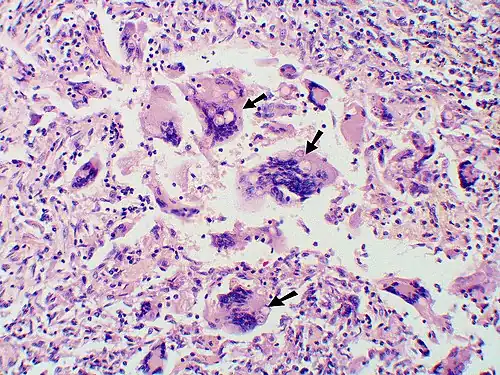

-

Large yeast-like fungi seen within giant cells at arrows.